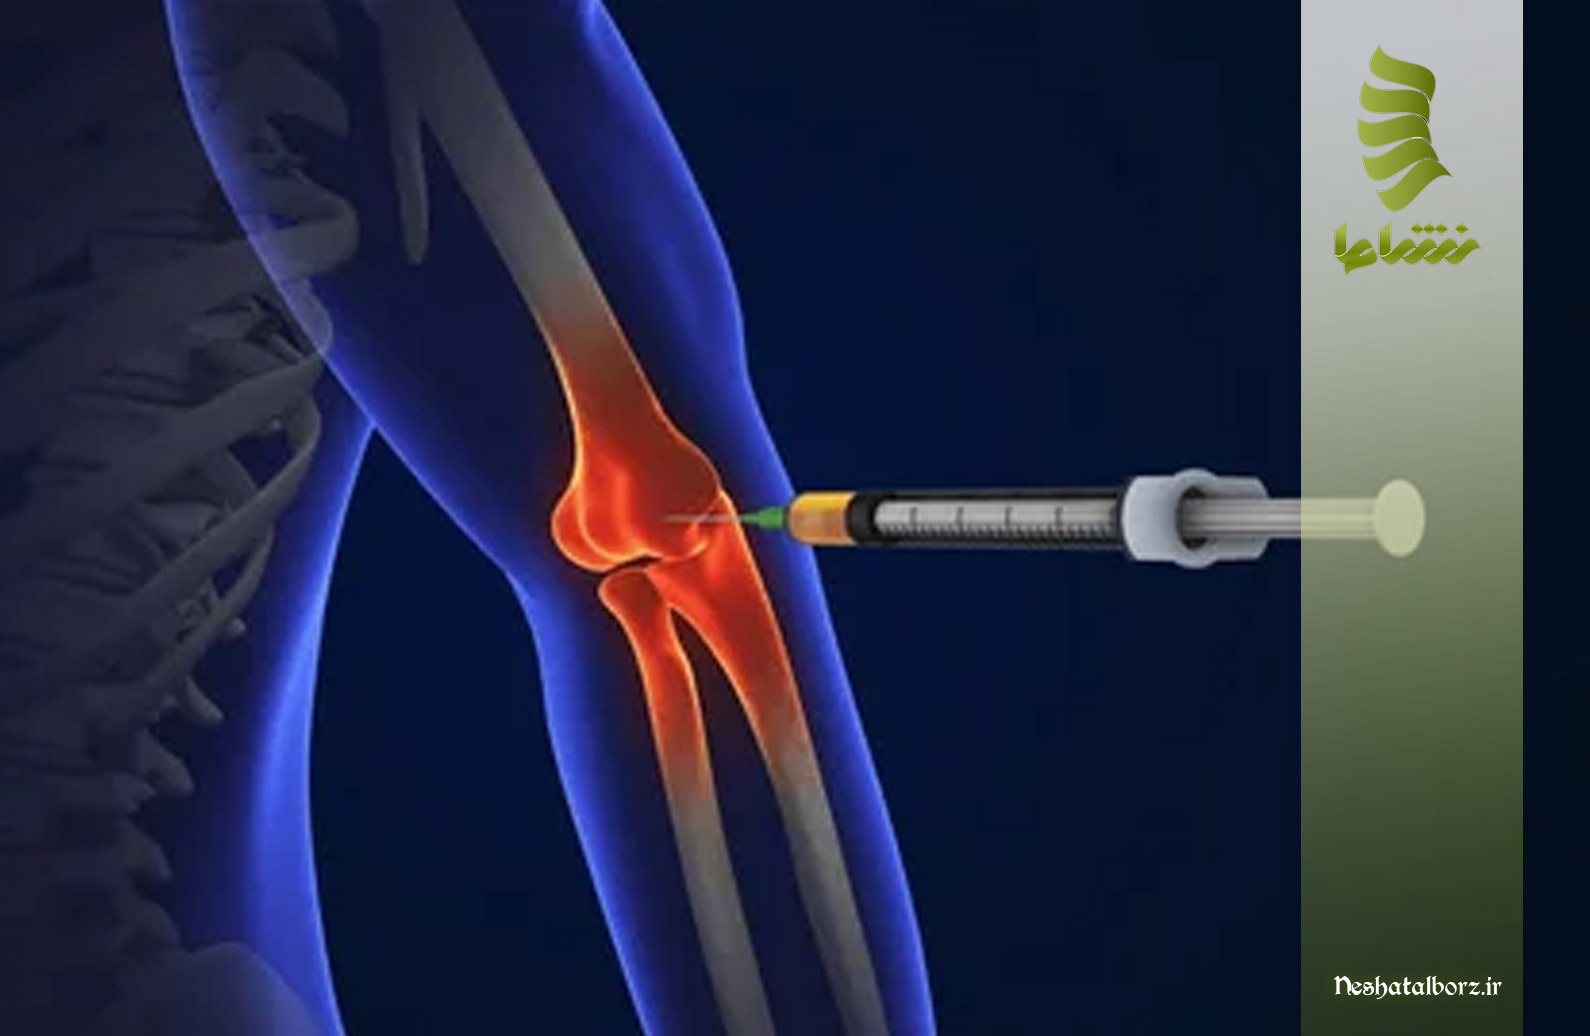

- تزریق پی آر پی برای درمان آرنج تنیس بازان: محلول پی آر پی که حاوی پلاکتهای تغلیظ شده است، با استفاده از سوزنهای نازک و دقیق به ناحیه آسیبدیده یا مفصل هدف تزریق میشود. درمان آرنج تنیس بازان با پی آر پی به دقت بالا و تخصص پزشک نیاز دارد تا از قرارگیری صحیح و موثر آن اطمینان حاصل شود.